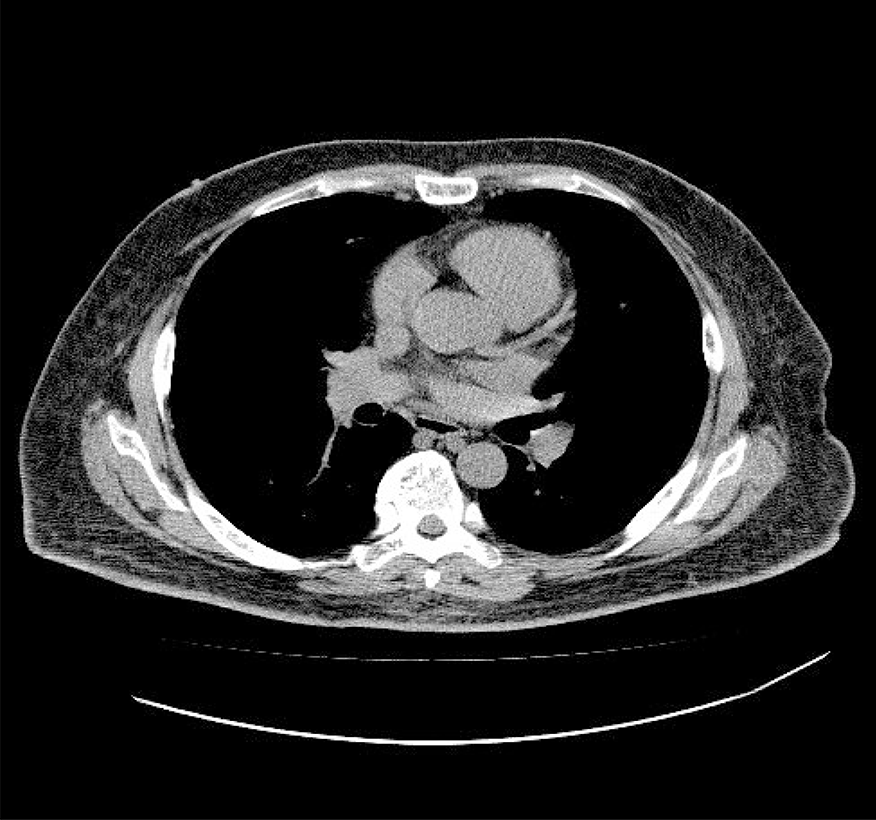

胸部CT

通常の胸部レントゲンに比べて

断面像のため心臓や肋骨に隠れた小さな早期病変を発見できます。肺がんだけでなく、肺気腫や心臓、血管に起こる様々な病気の早期発見が可能です。

画像から以下のような疾患が見つかる可能性があります!

肺に関係する疾患

・肺癌 慢性閉塞性肺疾患(COPD)

・アスベスト肺 肺結核 肺炎

心臓・血管に関する疾患

・冠動脈疾患(冠動脈石灰化病変)

心拡大

・胸部大動脈瘤